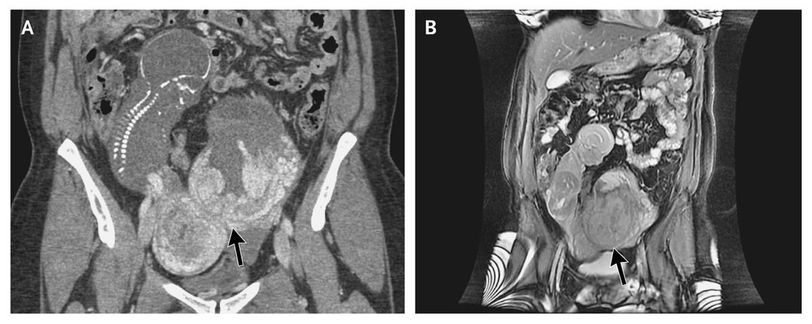

A 30-year-old woman who had a history of two pregnancies and one birth presented with an uncomplicated pregnancy until routine ultrasonography at 19 weeks revealed severe oligohydramnios and a fetus that appeared to be extrauterine. Computed tomography (Panel A) and magnetic resonance imaging (Panel B) of the abdomen and pelvis confirmed an abdominal ectopic pregnancy, with no uterine wall visible surrounding the pregnancy. The fetus was visualized in the right abdomen with a crown-to-rump length of 14 cm, with the placenta attached to the serosa of the uterine fundus (Panel A, arrow). No amniotic fluid surrounded the fetus. The pregnancy was terminated, and surgical removal of the fetus was performed. An abdominal pregnancy refers to a pregnancy that has implanted in the peritoneal cavity, external to the uterine cavity and fallopian tubes. In contrast to tubal ectopic pregnancies, abdominal pregnancies may go undetected until an advanced gestational age. Abdominal pregnancies are associated with a high rate of maternal complications.